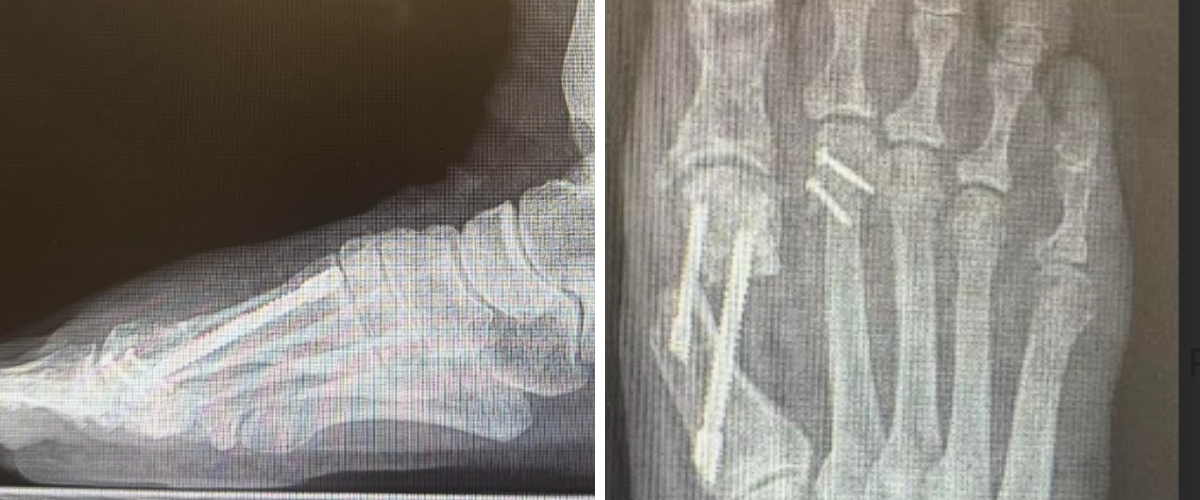

Oblique Metatarsal Osteotomy

For patients with transverse-plane deformity—including crossover toes, digital overlap, or windswept deformities—we prefer an oblique style osteotomy. This technique enables simultaneous shortening and medial or lateral translation of the metatarsal head, thereby improving tendon balance and MTPJ alignment.

Surgical Technique. We perform a linear capsulotomy, exposing the metatarsal head and neck. Transection of the lateral collateral ligaments facilitates reduction of the capital fragment. We avoid using a McGlamry elevator to protect the articular cartilage. Retractors placed around the metatarsal assist with controlled exposure.7

For medial translations (eg, medial crossover second toe), the osteotomy begins at the lateral aspect of the metatarsal head just proximal to the articular surface and exits proximal at the medial cortex in an oblique fashion. For lateral translations (eg, windswept toe deformity), the osteotomy begins at the medial aspect of the metatarsal head just proximal to the articular surface and exits proximally at the lateral cortex in an oblique fashion.

After freeing the capital fragment, shortening can take place as needed, and the surgeon can adjust the sagittal plane position by plantarflexing or dorsiflexing the head. Frequent fluoroscopic evaluation helps confirm correction and alignment. As the capital fragment naturally translates proximally, it realigns the metatarsal phalangeal joint, reducing the tendon imbalance which can cause toe deformity. Fixation uses two snap-off screws placed perpendicular to the osteotomy. The surgeon should remodeling the distal metatarsal to eliminate any step-off distally. Soft tissue balancing and hammertoe correction can then take place as indicated, adding temporary MTPJ pinning if desired to enhance postoperative stability.

The oblique metatarsal osteotomy provides the versatility of simultaneous shortening and transverse-plane correction, making it ideal for deformities involving digital overlap, windswept toes, or combined MTPJ instability.